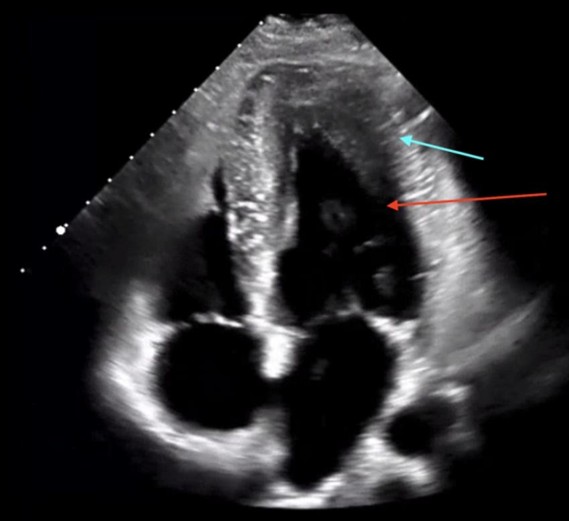

Figure 2. Transthoracic echocardiogram, Apical 4 Chamber view showing the localized several apical segment hypertrophy of the left ventricle (blue arrow). There is also the characteristic “ace of spades” geometry, reflective of systolic obliteration of the apex (red arrow).